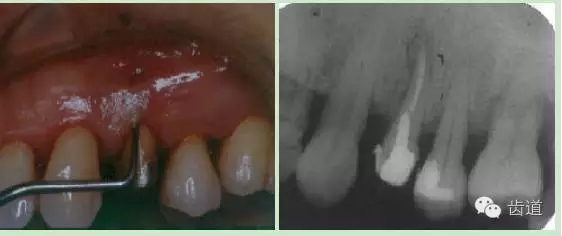

頰側(cè)牙齦相應(yīng)于根中部可見瘺管,周圍齦腫脹,輕壓少量溢膿。

瘺管處尖探針探入可達根面,略有粗糙感。

PD 頰側(cè)正中10mm,窄而深,袋口緊,附著喪失9 mm。探與瘺管相通,鄰面及腭側(cè)PD 3-4 mm,樁核冠,未粘合,正中咬合輕度早接觸。松動 Ⅰ°全口口腔衛(wèi)生較差,PLI: 2,牙石(++)

彩幻及X片: